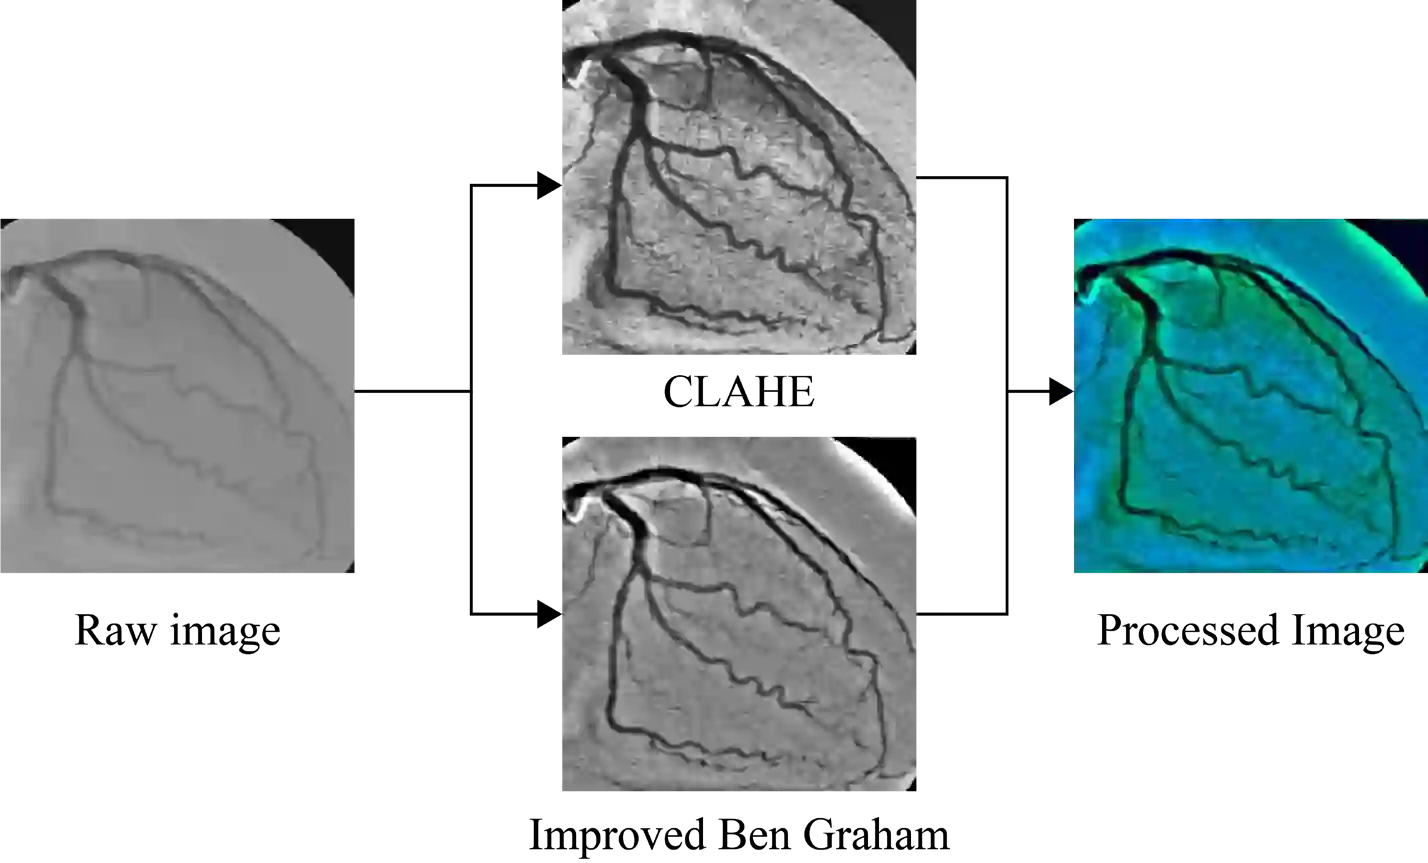

Early detection of coronary artery disease (CAD) is critical for reducing mortality and improving patient treatment planning. While angiographic image analysis from X-rays is a common and cost-effective method for identifying cardiac abnormalities, including stenotic coronary arteries, poor image quality can significantly impede clinical diagnosis. We present the Coronary Artery Segmentation and Refinement Network (CASR-Net), a three-stage pipeline comprising image preprocessing, segmentation, and refinement. A novel multichannel preprocessing strategy combining CLAHE and an improved Ben Graham method provides incremental gains, increasing Dice Score Coefficient (DSC) by 0.31-0.89% and Intersection over Union (IoU) by 0.40-1.16% compared with using the techniques individually. The core innovation is a segmentation network built on a UNet with a DenseNet121 encoder and a Self-organized Operational Neural Network (Self-ONN) based decoder, which preserves the continuity of narrow and stenotic vessel branches. A final contour refinement module further suppresses false positives. Evaluated with 5-fold cross-validation on a combination of two public datasets that contain both healthy and stenotic arteries, CASR-Net outperformed several state-of-the-art models, achieving an IoU of 61.43%, a DSC of 76.10%, and clDice of 79.36%. These results highlight a robust approach to automated coronary artery segmentation, offering a valuable tool to support clinicians in diagnosis and treatment planning.